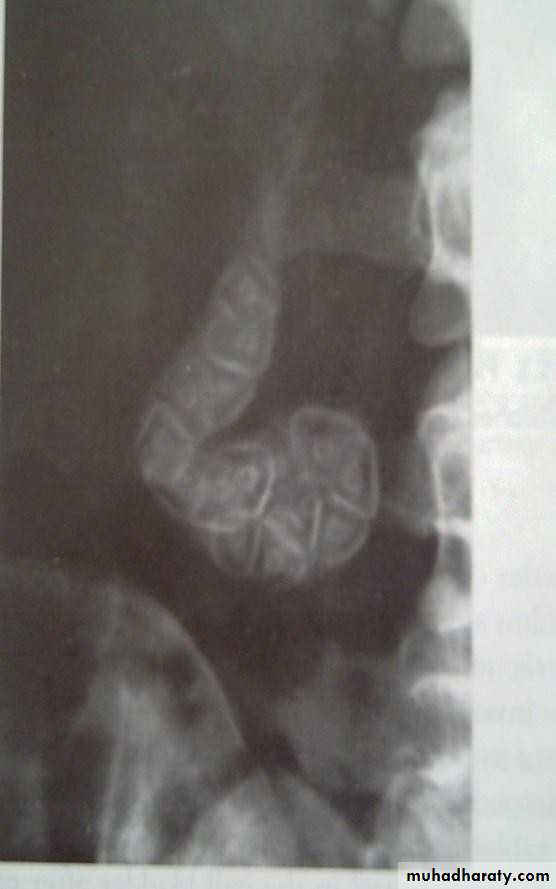

• CT SCAN

• Computed tomography scan demonstrating a gallstone

• within the gall bladder (arrowed).• Magnetic Resonance Cholangiopancreatograph: